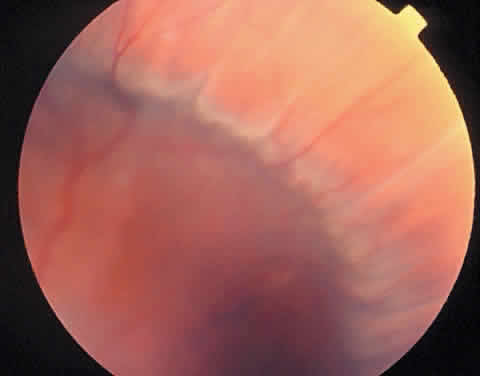

Scleral buckles placed for the repair of retinal detachment can cause chorioretinal folds. These folds are seen perpendicular to the buckle, and they may be exacerbated by the presence of a serous choroidal detachment (Fig. 6).

Fig. 6. Encircling scleral buckles placed for the repair of retinal detachments can cause chorioretinal folds perpendicular to the orientation of the buckle. In this photograph, the folds are exacerbated by a concurrent serous choroidal detachment.